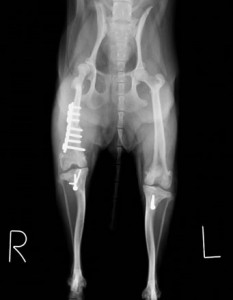

大腿骨の骨きりおよびプレートにて矯正しました。滑車溝も形成を行いました。

最後に脛骨粗面の転植し、大腿骨-膝蓋骨-脛骨粗面のアライメントと整え手術終了としました。

手術後レントゲン:膝蓋骨は正常な位置に整復され、足もまっすぐになりました。 術後は1週間程で歩行できるようになり、2ヶ月ほどでほぼ正常なワンちゃんと変わらず元気に遊べるようになりました。膝蓋骨内方脱臼は先天的疾患で、このワンちゃんほど重度な症例は珍しいですが、比較的小型犬に多い後肢の疾患です。膝蓋骨がすでに脱臼しているが症状が無いわんちゃんも多く認められます。安易な経過観察は関節炎や前十字靭帯断裂症など様々な合併症の原因となるため、比較的早期の整復手術をおすすめします!